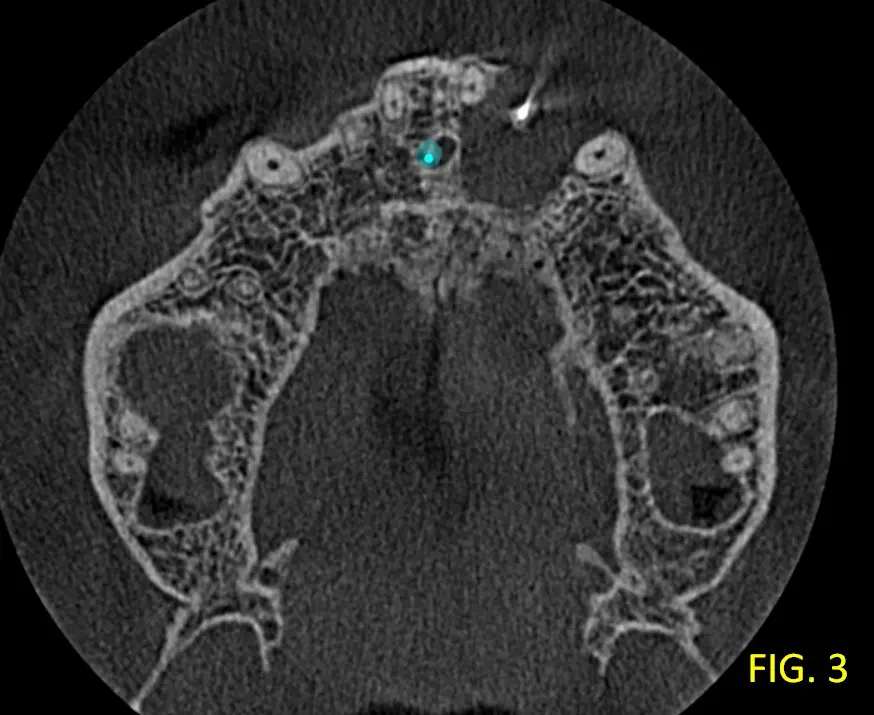

Su contenido es homogéneo, sin tabiques ni calcificaciones. No se observa invasión del piso de fosas nasales ni desplazamiento significativo de raíces vecinas. En el corte transaxial, fig. 2 se confirma la ubicación periapical exacta de la lesión, asociada a la pieza 22 donde se evidencia que la lesión es unilocular y no atraviesa estructuras anatómicas mayores. En la fig. 3, vista axial se observa la ausencia de la tabla ósea vestibular.